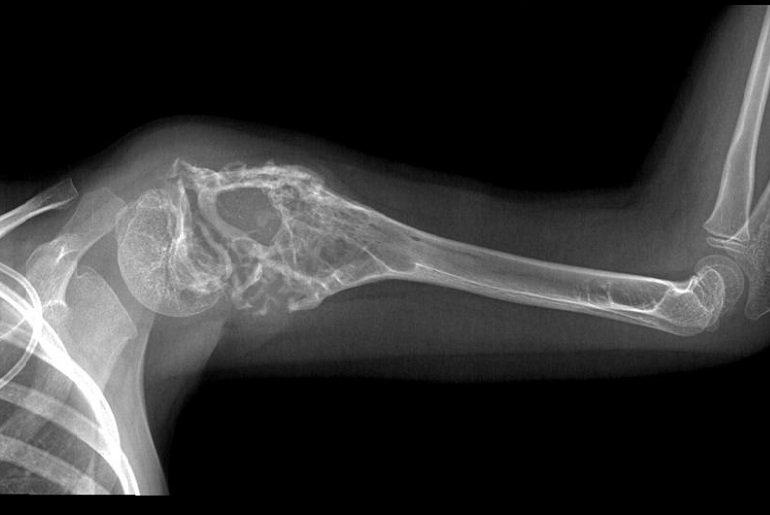

Диагностика саркомы

После визуального осмотра и сбора медицинской информации специалист назначает диагностические процедуры для оценки размеров опухолей. Для более точного определения диагноза могут быть рекомендованы следующие исследования:

- рентгенография;